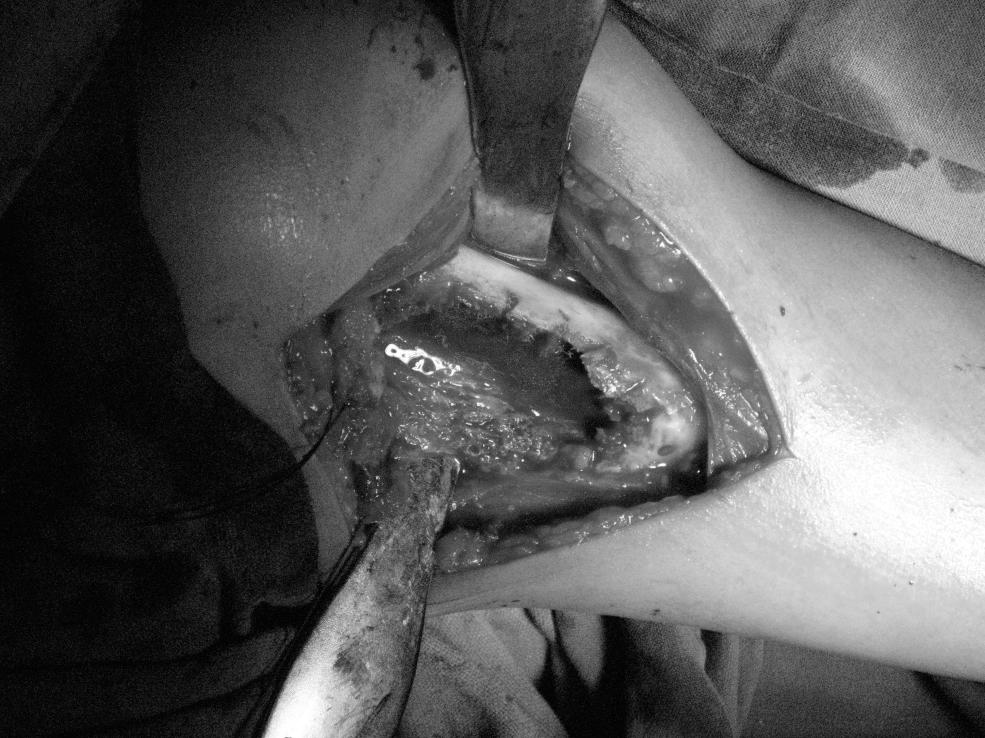

Per operative

The biopsy confirmed the diagnosis

AFTER REMOVAL